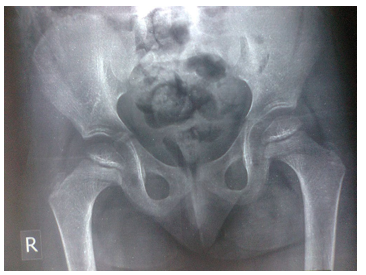

Old radiographs of the younger sister showed osteopenia, fracture in the upper limb, and progressive bowing with no rachitic changes. Figure-3A and 3B show lower limb radiographs showing progressive bowing. Figure-4 (A, B, C, and D) show recent bone radiographs of the younger sister taken during May, 2023 which showed osteopenia, bowing with no rachitic changes. Radiograph of the pelvis showed mild protrusio acetabula (Figure-4A). Radiograph of the wrist showed no rachitic changes (Figure-4B). Radiograph of the lower limbs showed bowing, cortical thinning with scanty spongiosa (Figure- 4C). Lateral skull radiographs showed platybasia (Figure-4D).

Figure-4A: Radiograph of the pelvis showing mild protrusio acetabula